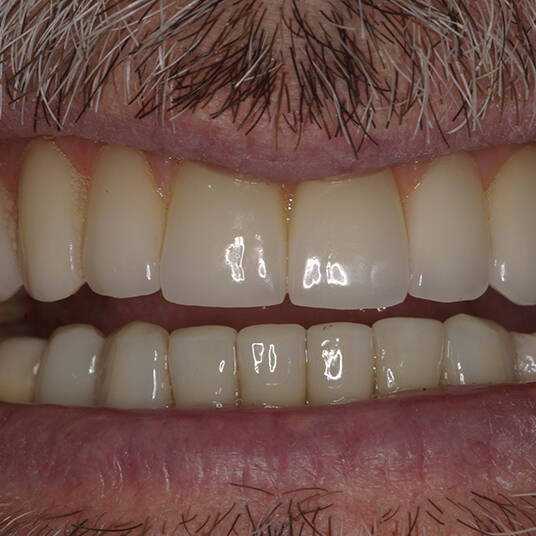

Na Clínica Pontes Odontologia, somos referência em implantes dentários em Fortaleza, oferecendo tratamentos de alta qualidade e tecnologia de ponta. Os implantes dentários são estruturas de titânio posicionadas cirurgicamente no osso maxilar ou mandibular para substituir as raízes dos dentes ausentes. Essa técnica permite a fixação de próteses personalizadas, restaurando a função mastigatória, a estética e a autoestima dos nossos pacientes.

Nosso compromisso é oferecer um tratamento de excelência, com profissionais especializados e tecnologia de última geração para implantes dentários em Fortaleza. Venha nos visitar e descubra por que a Clínica Pontes Odontologia é referência em implantes dentários em Fortaleza, devolvendo sorrisos e qualidade de vida aos nossos pacientes.